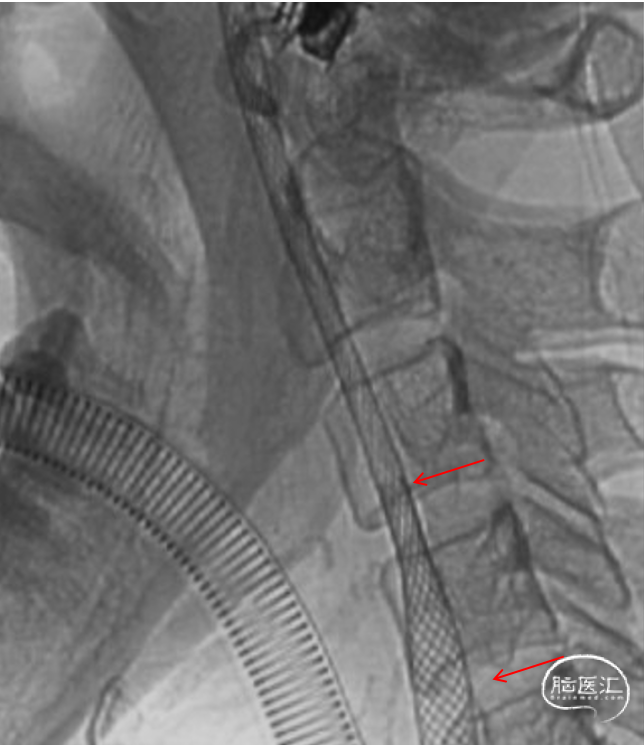

6F Envoy导引导管到位后,微导丝通过闭塞段,引导微导管到达C6段,造影确认真腔

璞慧微导丝技术送至M1段,撤出微导管送入Sacspeed 2.5/15:Sacspeed 2.5mm/15mm球囊自远及近扩张

球扩成型后,依次植入Wallstent 7/50、7/30

C1段支架成型满意,但C3段仍狭窄,植入Apollo 3/23球扩支架